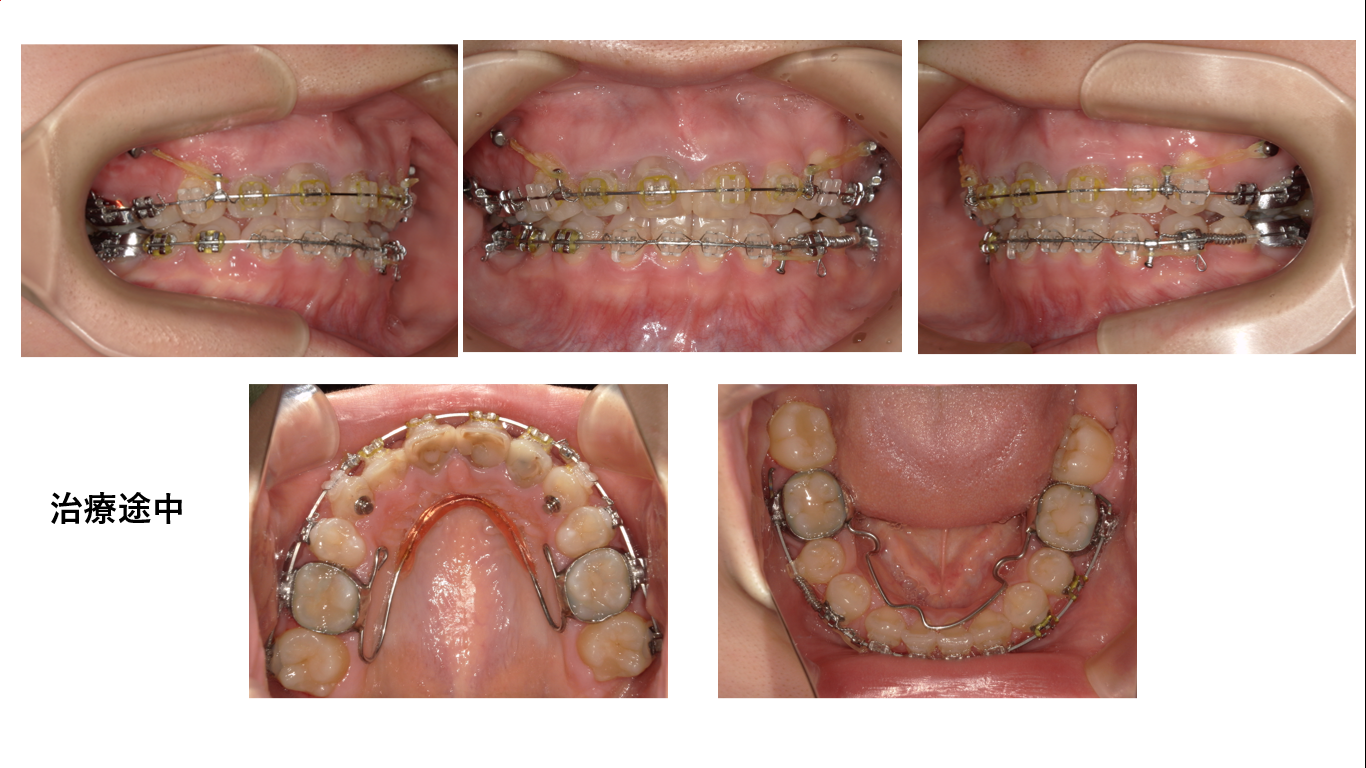

上の写真は治療開始から1年が過ぎたところです。